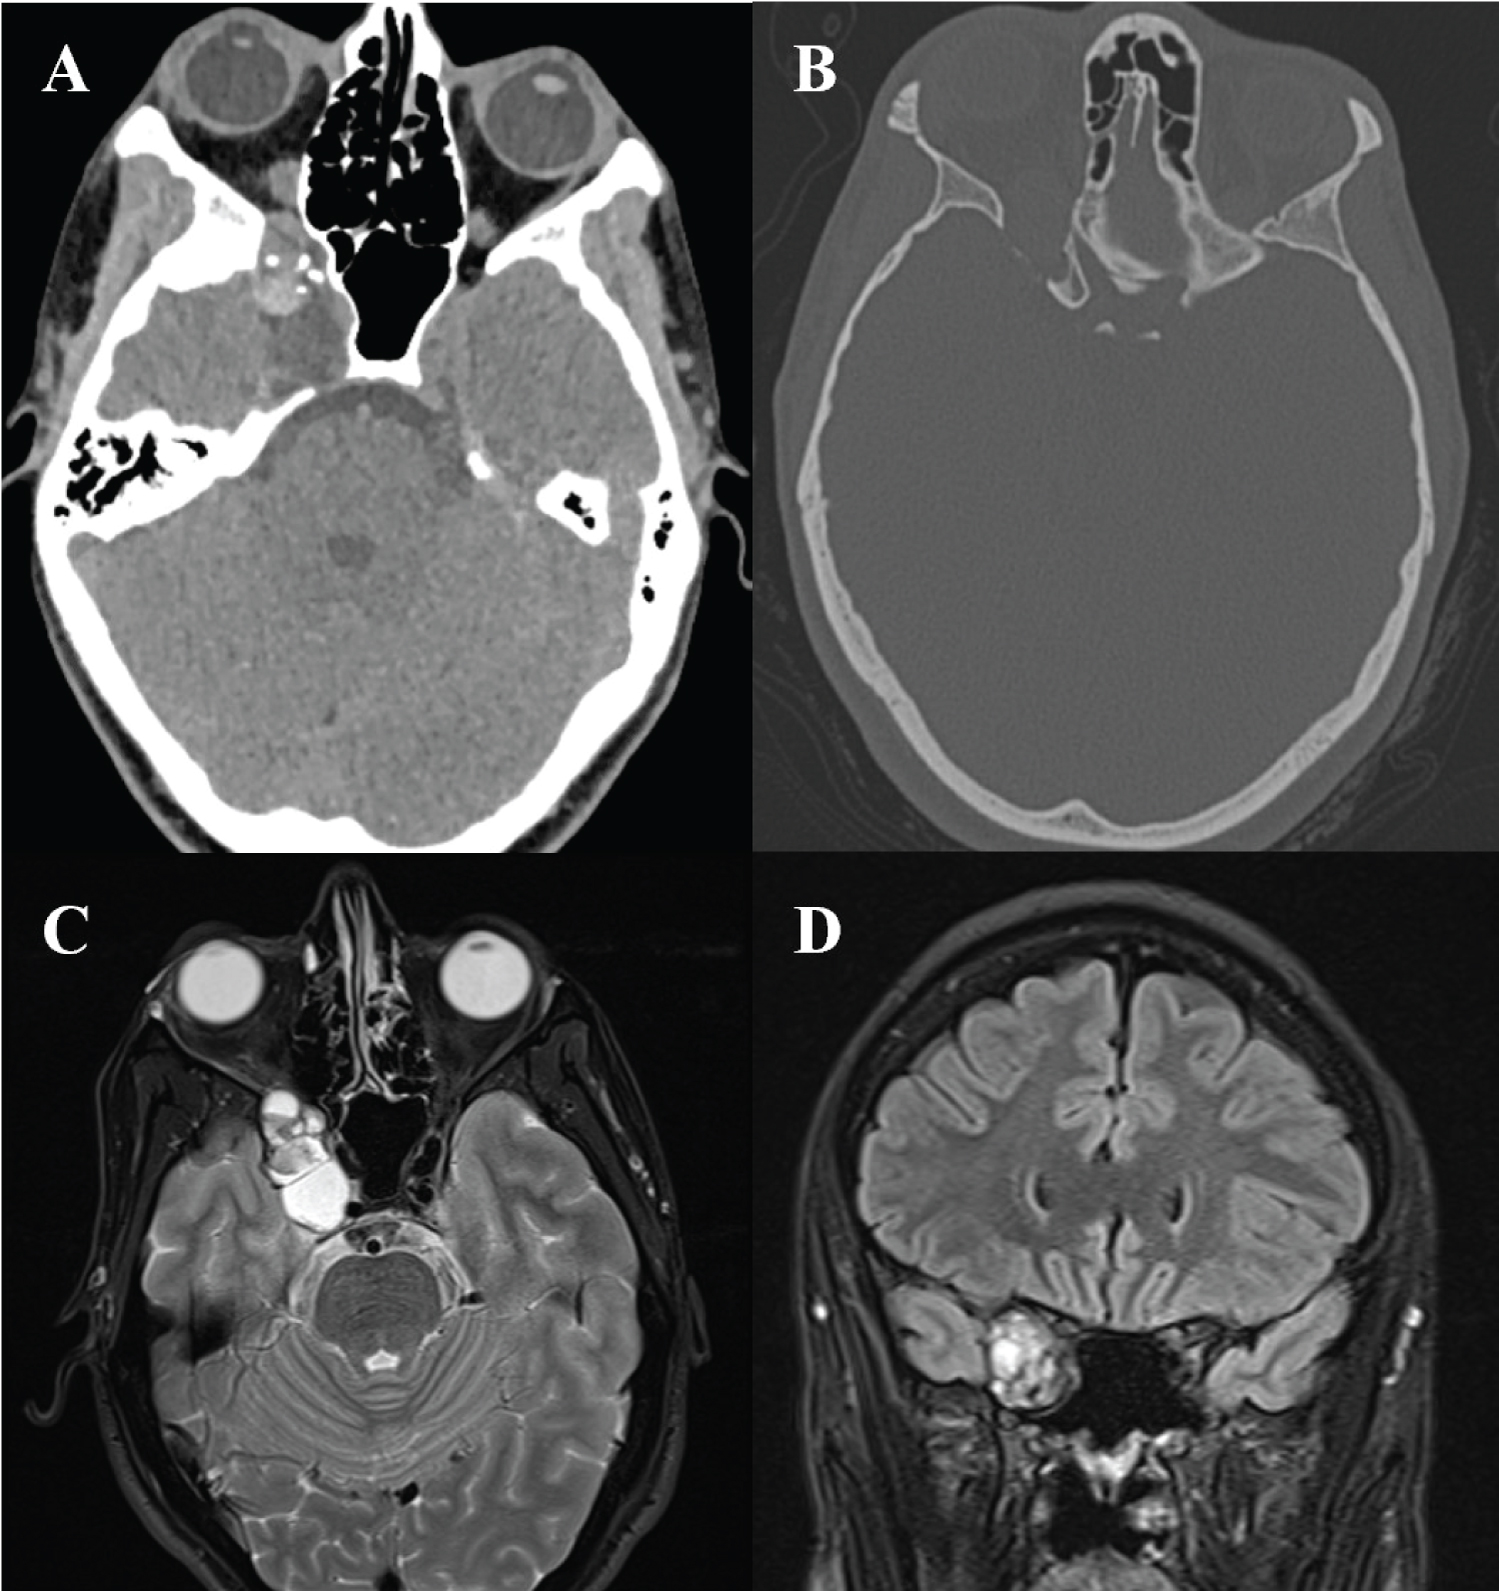

On presentation, CT imaging demonstrated a multicystic osseous lesion arising from the right sphenoid wing and extending into the right orbit with hyperdense components ventrally consistent with hemorrhage and smooth scalloping and thinning of the sphenoid bone and anterior clinoid process. MRI brain demonstrated a 3.8 × 1.8 × 2.7 cm cystic lesion with peripheral enhancement centered in the right superior orbital fissure with widening of the fissure (Figure 1). The lesion was predominantly T2 hyperintense, although there were some areas of T2 hypointensity and T1 hyperintensity consistent with subacute hemorrhage. Based on imaging, the differential diagnosis included a vena lymphatic malformation, schwannoma, and less likely dermoid tumor, and direct cranial nerve involvement was not anticipated.

Figure 1: A) Axial non-contrast CT demonstrating the mixed density lesion centered within the orbital apex with hyperdense components posteriorly likely representing hemorrhage and scattered calcification; B) Axial CT bone window demonstrating smooth bony remodeling and expansion; C-D) T2-weighted axial; C) Coronal; D) MRI demonstrating a 3.8 × 1.8 × 2.7 cm hyperintense cystic mass centered within and causing widening of the superior orbital fissure, extending through the annulus of Zinn and into the right posterior orbit. View Figure 1

The average age at diagnosis of NMC was 25.8 years (range 2 to 68), without sex predilection. This tumor is most often associated with certain cranial nerves; most commonly the eighth cranial nerve, followed by the fifth, seventh, third and second nerves. Given involvement of the superior orbital fissure, the tumor in our case was intimately involved with multiple cranial nerves (III, IV, V1) which had not been described before. Symptoms often progress over months to years. Our review showed an average duration of 4.1 years with our case as the most rapidly progressive due to intralesional hemorrhage. Diagnosis of choristoma remains difficult. Imaging characteristics appear to be highly heterogenous, although many enhance with contrast, albeit in an inconsistent pattern [11]. As in our case, there is often benign expansion of the surrounding bony structures with smooth scalloping due to slow growth. The characteristic microscopic appearance is nests and fascicles of well-differentiated striated or smooth muscle with intermixed neural fibers in a perimysium sheath [2,26].